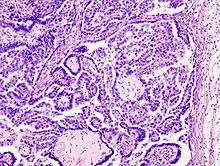

Pathology

- Epithelial tumors - most common, 65%

- Serous tumors: 25% of ovarian tumors, 40% of epithelial tumors

- Benign (60%): Serous cystadenoma, cystadenofibroma

- Borderline (15%): Serous borderline tumors, microinvasive serous carcinoma

- Malignant (25%): Serous cystadenocarcinoma, serous carcinoma, serous micropapillary carcinoma, serous psammomacarcinoma

- Mucinous tumors: 15% of ovarian tumors, 25% of epithelial tumors

- Benign (80%): Mucinous cystadenoma, mucinous adenofibroma

- Borderline (10%): Mucinous borderline tumors, microinvasive mucinous carcinoma

- Malignant (10%): Mucinous cystadenocarcinoma, mucinous carcinoma

- Endometrioid tumors: 20% of ovarian tumors, 35% of epithelial tumors

- Benign: Endometrioid cystadenoma, endometrioid adenofibroma

- Borderline: Endometrioid borderline tumors

- Malignant (Majority): Endometrioid carcinoma

- Brenner tumors (benign, borderline, or malignant) - composed of urothelial-like cells

- Other: Clear cell adenocarcinoma, urothelial carcinoma (transitional cell), mixed epithelial-papillary cystadenoma of borderline malignancy of mullerian type